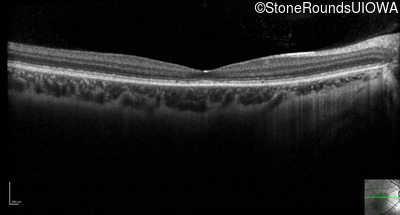

Optical Coherence Tomography - Right - 20/32 -2 sc

Exemplar / OCT Stack

Optical Coherence Tomography - Left - 20/25 -2 sc